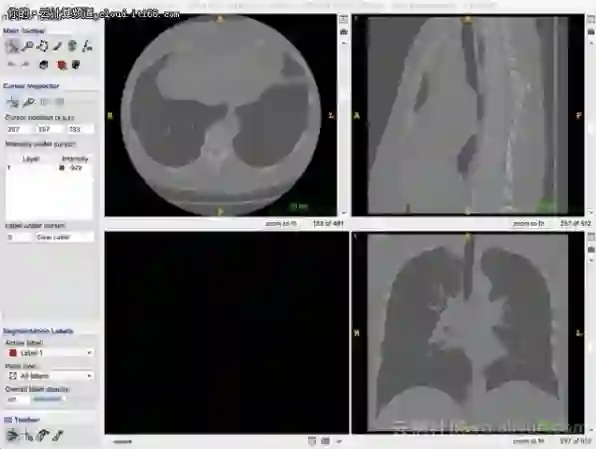

肺部CT资料

国家癌症中心公布的数字显示,肺癌在所有恶性肿瘤发病及死亡中均占首位。胸部CT放射影像技术,是肺癌早期筛查的有效手段。但是由于CT扫描影像数量多(一次CT扫描影像通常在200张以上),医生诊断的时间长,加上工作量大,容易疲劳,人工误差不可避免。人工智能成为新的选择。